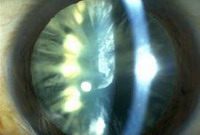

Рубеоз![]() Рубеоз обозначает патологический рост сосудов на радужке (неоваскуляризация радужки) и в углу передней камеры (пространстве между роговицей и радужк... |